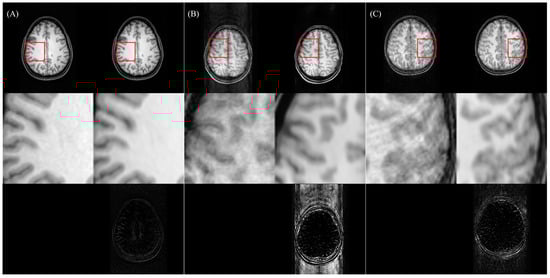

5.1. Advantages of Two-Stage Training and Multiple-Loss Function